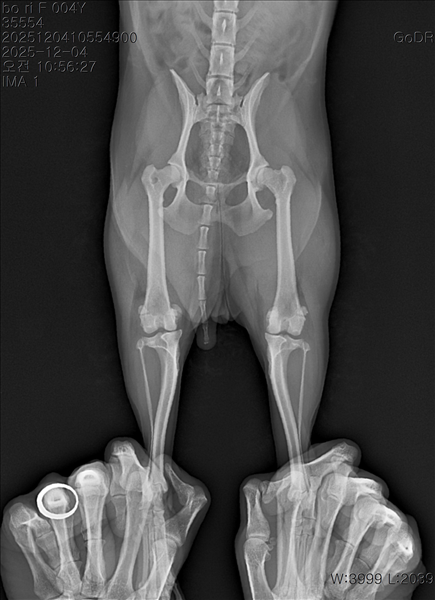

강아지 슬개골탈구 진단 받았습니다 몇군데 병원을 다녀봤는데 진단이 달라 궁금해서 질문 해봅니다 일단 저희 강아지는 오른쪽 다리를 갑자기 들고 다니고 절어 병원을 방문하게 되었고요 왼쪽은 증상이 없지만 오른쪽만 있는 상태였습니다 첫번째랑 두번째 병원에서는 슬개골 탈구 진행중이고 왼쪽이 3기 오른쪽이 2기 정도라고 했습니다 하지만 왼쪽은 아예 빠져있어 증상도 없고 아파하지도 않는다고 했고 오른쪽은 빠졌다 안빠졌다 해서 증상이 있다고 했고 십자인대가 파열된 걸론 보이지 않는다고 했습니다 그래서 양쪽 슬개골탈구 수술만 진행하면 된다고 했고요 근데 세번째 병원에서는 둘다 왼쪽이 좀 더 심한 슬개골 탈구 3기 정도라고 했고 오른쪽만 십자인대 부분파열이 보인다고 했습니다 그래서 십자인대 파열이 아닌 왼쪽은 굳이 수술할 필요가 없고 나중에 십자인대 파열이 오거나 증상이 나타나면 그때 수술하면 된다고 했습니다 그래서 오른쪽 슬개골탈구 수술과 tplo를 하는 방식으로 수술을 한다고 했습니다 여기서 궁금한점은

1. 십자인대 파열이 사진상으론 보이지 않는다고 하는데 사진상으로 알 수 있는 건가요?

2. 십자인대 파열이 아니면 슬개골탈구 수술을 굳이 할 필요 없다고 하셨는데 맞는 건가요?

3. 꼭 슬개골탈구와 십자인대 수술을 같이 해야 결과과 더 좋아지나요?

4. 사진상으로 십자인대와 슬개골 수술을 같이 해야할까요? 5. tplo 수술방법이 가장 안전하고 좋은 수술방법인가요?

6. 슬개골탈구로 인해 십자인대가 끊어지는건 아니라고 들었는데 맞나요? 슬개골 탈구 수술로 십자인대를 예방할 수 있나요?